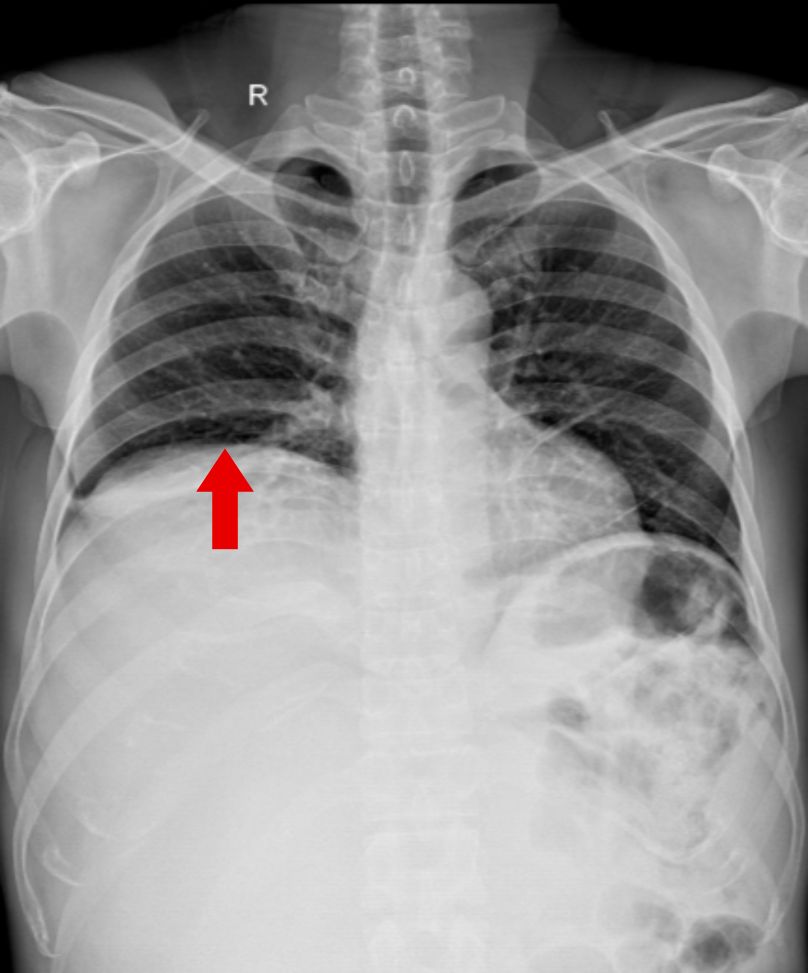

Phát hiện bất thường từ triệu chứng vàng da Bệnh nhân nữ, 59 tuổi, nhập viện trong tình trạng vàng da, ngứa và đau vùng hạ sườn phải kéo dài. Kết quả chẩn đoán hình ảnh cho thấy tổn thương đường mật trong gan kèm sỏi và giãn đường mật. Trong quá trình thăm khám… Xem thêm